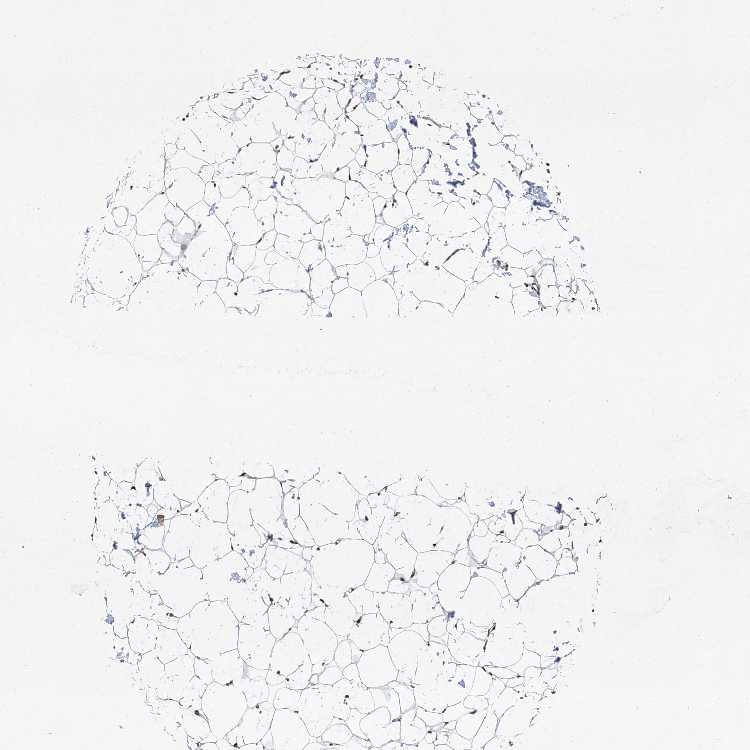

SOFT TISSUE 2 - Antibody stainingi

Antibody staining in the annotated cell types in the current human tissue is reported as not detected, low, medium, or high, based on conventional immunohistochemistry profiling in selected tissues. This score is based on the combination of the staining intensity and fraction of stained cells.

Each image is clickable and will lead to virtual microscopy that enables deeper exploration of all samples and also displays staining intensity scores, fraction scores and subcellular localization as well as patient and tissue information for each sample.

Antibody HPA030813Antibody CAB032306

Chondrocytes HighNot detected

Fibroblasts MediumMedium

Peripheral nerve -Medium